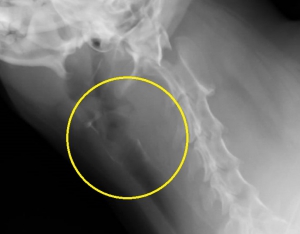

頸部レントゲンで、「異物が存在する」はずの黄色の丸で囲んだエリアには異常は認められません。

ここでバリウム造影検査を行ったものが下写真です。上の写真黄色のサークル内でほぼ見えない異物が造影剤で浮かび上がっているのがお分かりだと思います。異物は咽頭のすぐ下から食道に入って数センチ以内の場所に存在しているようです。